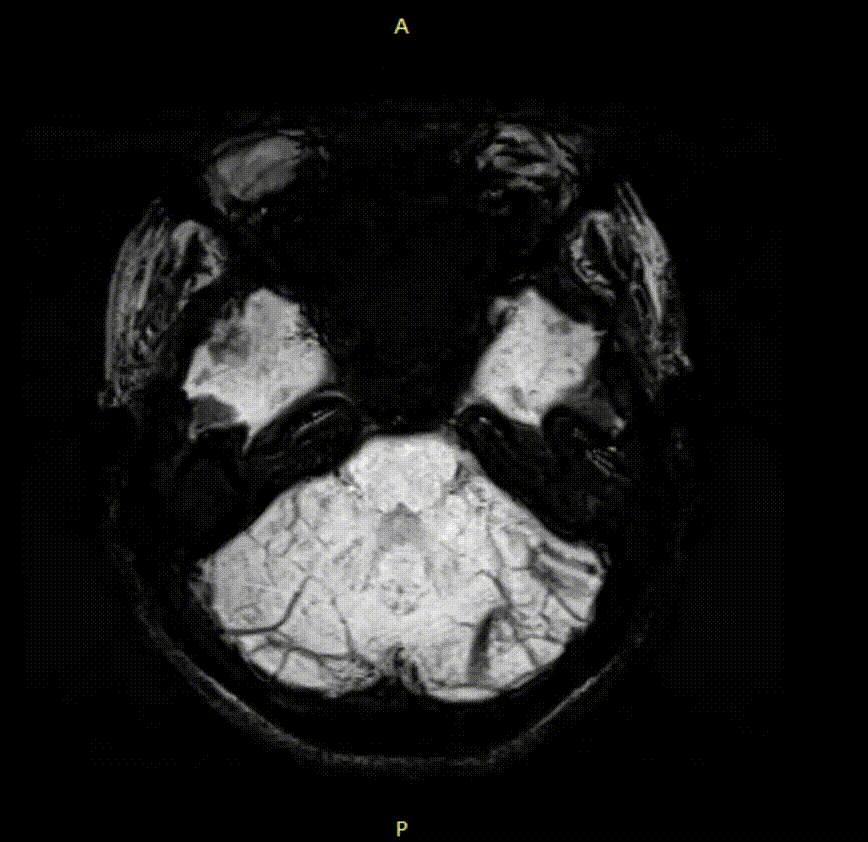

This is a collaboration between ScAN and the Australasian Association of Writing Programs (AAWP), the peak academic body representing the discipline of Creative Writing in Australasia. We invited creative writing responses to images of the living brain, from the ScAN Library, acquired using magnetic resonance imaging (MRI). Participants were sent a brain image and invited to respond in prose and poetry. Springboarding from the image, authors wrote about any subject matter they chose.

A selection of authors pieces were presented at the Organization of Human Brain Mapping (OHBM) 2021 Open Science Gala. These authors and their images are listed below. Click on a name or image to see an author’s contribution.